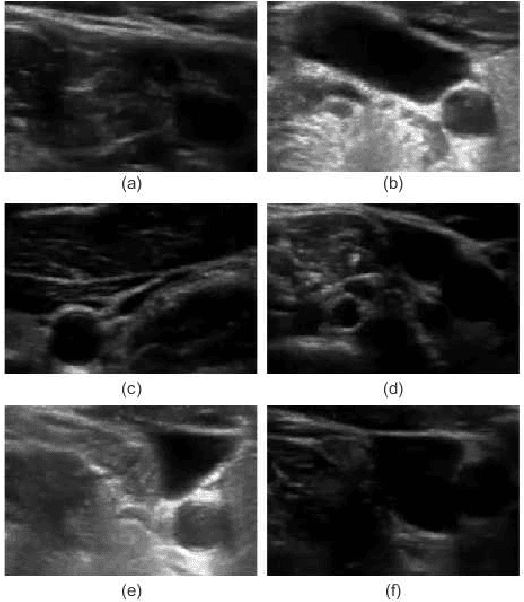

Abstract:Detection of relative changes in circulating blood volume is important to guide resuscitation and manage a variety of medical conditions including sepsis, trauma, dialysis and congestive heart failure. Recent studies have shown that estimates of circulating blood volume can be obtained from the cross-sectional area (CSA) of the internal jugular vein (IJV) from ultrasound images. However, accurate segmentation and tracking of the IJV in ultrasound imaging is a challenging task and is significantly influenced by a number of parameters such as the image quality, shape, and temporal variation. In this paper, we propose a novel adaptive polar active contour (Ad-PAC) algorithm for the segmentation and tracking of the IJV in ultrasound videos. In the proposed algorithm, the parameters of the Ad-PAC algorithm are adapted based on the results of segmentation in previous frames. The Ad-PAC algorithm is applied to 65 ultrasound videos captured from 13 healthy subjects, with each video containing 450 frames. The results show that spatial and temporal adaptation of the energy function significantly improves segmentation performance when compared to current state-of-the-art active contour algorithms.